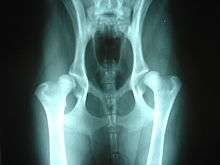

Hereditary orthopedic diseases are mainly found in purebred dogs. Hip dysplasia is a common problem that primarily affects larger breeds. Hip dysplasia is a defect in the shape of the hip joint which can, depending on the degree of hip luxation, be quite painful to the dog as it ages. Over time it often causes arthritis in the hips. Dysplasia can also occur in the elbow joint. Luxating patellas can be a problem for smaller breeds. It can cause lameness and pain in the hind legs.